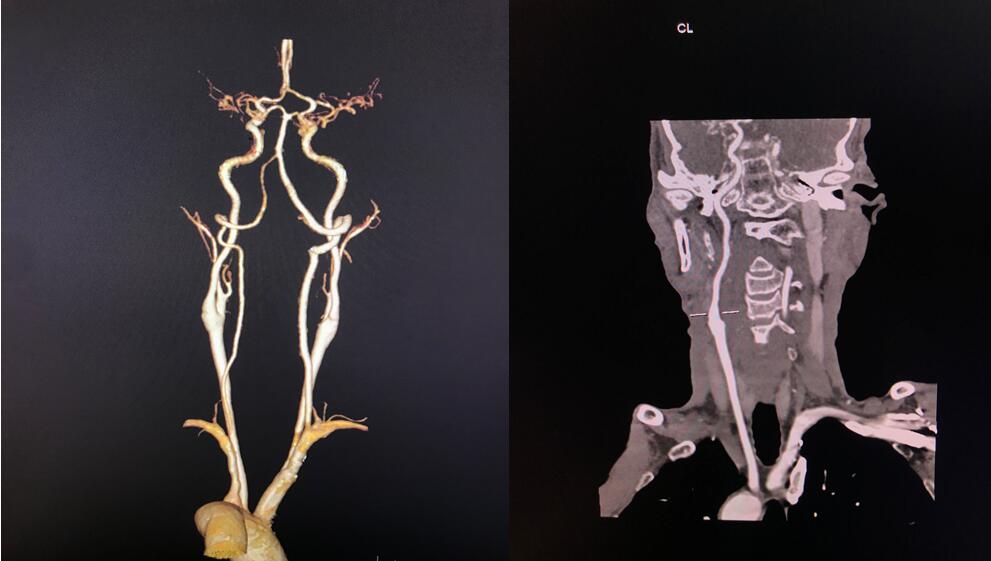

四、开展项目:科室现常规开展全身各部位CT平扫及增强检查、CT三维重建、CT血管造影(CTA、CTV)、(包括冠状动脉CTA)、CT尿路造影(CTU)、全身各部位DR摄片检查、床边摄片、同时开展胆系T管造影、CT定位下穿刺活检。

头颈CTA检查